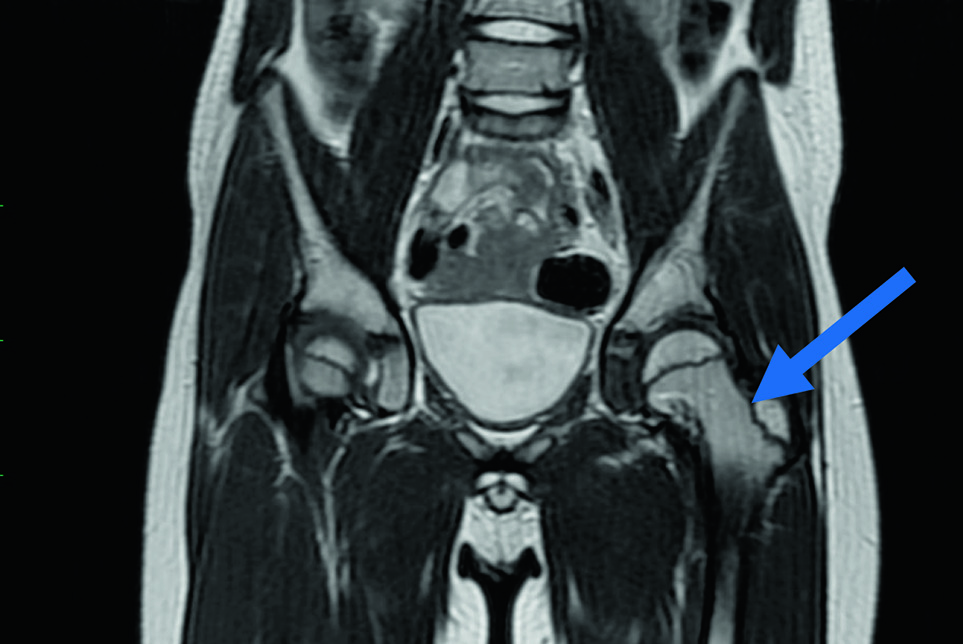

По данным МРТ тазобедренных суставов от 06.09.2024 в левой бедренной кости по медиальной поверхности выявлен субкортикальный участок изменения МР-сигнала с признаками остеосклероза по периферии, что характерно для перенесенного остеонекроза (рисунок 2).

Рисунок 2

Магнитно-резонансная томограмма тазобедренных суставов, Т2-взвешенное изображение: участок остеонекроза с признаками остеосклероза по периферии в левой бедренной кости указан стрелкой

Figure 2

A T2-weighted MR image of the hip joints: an area of osteonecrosis with signs of peripheral osteosclerosis in the left femur (indicated by the arrow)